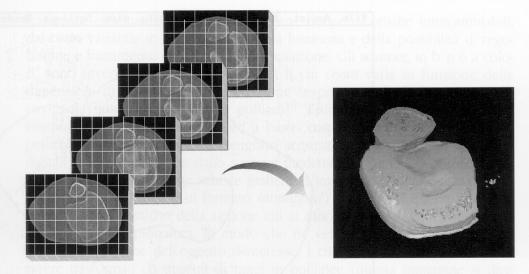

Tutti i programmi si basano su due tecniche di ricostruzione:  per superfici o per volumi[1].

La ricostruzione per superfici, mostrata in figura 1‑5, considera solamente i dati relativi alla superficie dell’oggetto, ignorandone la struttura. Una volta definito il profilo di interesse per ogni sezione, i dati residui possono essere eliminati. L'oggetto può quindi essere rappresen­tato come una sequenza di curve approssimanti (dette spline) impilate nello spazio, connesse da un mosaico di poligoni (usual­mente triangoli) o intercettate da una superficie complessa.

Figura 15 Ricostruzione per superfici

La tecnica di ricostruzione volumetrica, mostrata in figura 1‑6, invece  ricostrui­sce spazialmente sia la superficie sia la struttura dell'oggetto, impiegando una matrice 3D di voxel[2]. Se dal punto di vista della rappresentazione grafica il risultato può essere ana­logo con entrambe le tecniche, ben diversi sono il numero di informazioni contenute nella ricostruzione 3D dell'oggetto - la sola superficie nel primo caso, superficie e struttura nel secondo - e, di conseguenza, le possibilità di ulterio­re elaborazione.